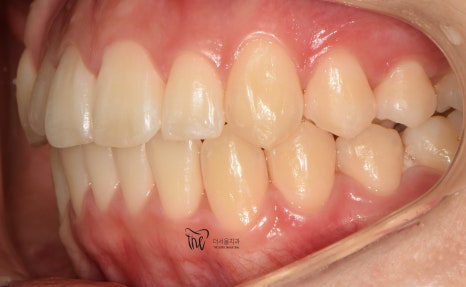

그러나, 좌측에서 바라봤을 때는 어금니들이

부정교합을 띄고 있는 것을 볼 수 있습니다.

즉, 거꾸로 물리는 반대교합의 양상을 보여주고

있고 이런 증세 때문에 턱관절의 통증까지도

조금씩, 치열이 가지런해지는 것을 볼 수 있으며

이미 여기 시점으로부터 어금니들이 서로

거꾸로 물리는 반대교합의 양상은 사라졌습니다.